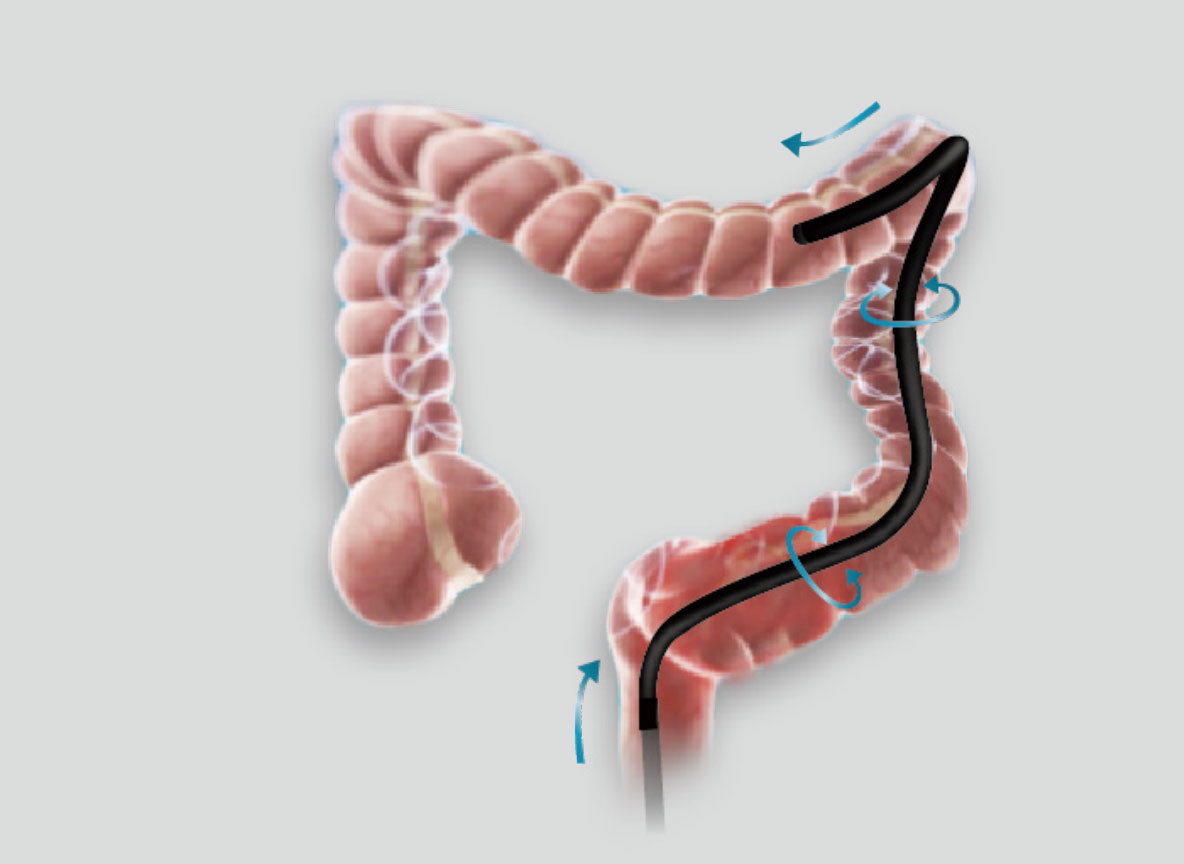

优秀的操控性和进镜性能

• 大弯曲角度

弯曲角度大,方便观察食管下段贲门、胃底部等难以观察到的部位,减少盲区。

• 高传导性分段硬度插入设计

带来镜体插入及诊疗新体验。